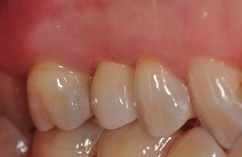

Die mit dem Abutment verklebten Restaurationen konnten nun entnommen, Zementüberschüsse (Abb. 22) sicher entfernt und die Übergänge von Krone zu Abutment poliert werden. Für die definitive Eingliederung ist der für die Abutmentschraube vorgegebene Anzugstorque von 25 Ncm einzuhalten. Nach erneutem Auffüllen der Schraubenkanäle wiederum mit Teflonband wurden die Zugangskavitäten in ebenfalls üblicher Weise mit Komposit verschlossen. Das Ergebnis sind im vorliegenden Fall 2 metall- und zementfreie, verschraubte und reversible Einzelzahnrestaurationen (Abb. 23). Bei dem routinemäßig durchgeführten Follow-up 6 Monate nach Eingliederung zeigte sich eine an beiden Implantatpositionen reizlose Weichgewebssituation (Abb. 24a und b) und in den radiologischen Kontrollaufnahmen stabile periimplantäre Knochenverhältnisse (Abb. 25a und b).